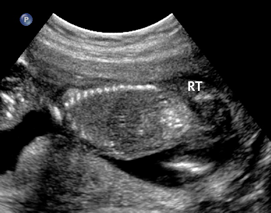

Above. Meconium peritonitis. Case 1. 36 6/7 weeks gestation. Transverse small bowel. Note small bowel dilatation and polyhydramnios.

Above. Meconium peritonitis. Case 1. 36 6/7 weeks gestation. Longitudinal small bowel. Note small bowel dilatation and mesenteric calcifications.

Above. Meconium peritonitis. Case 1. 36 6/7 weeks gestation. Again, note small bowel dilatation and mesenteric calcifications.

Above. Meconium peritonitis. Case 1. 36 6/7 weeks gestation. Note hepatic capsular calcifications and the presence of fetal ascites.